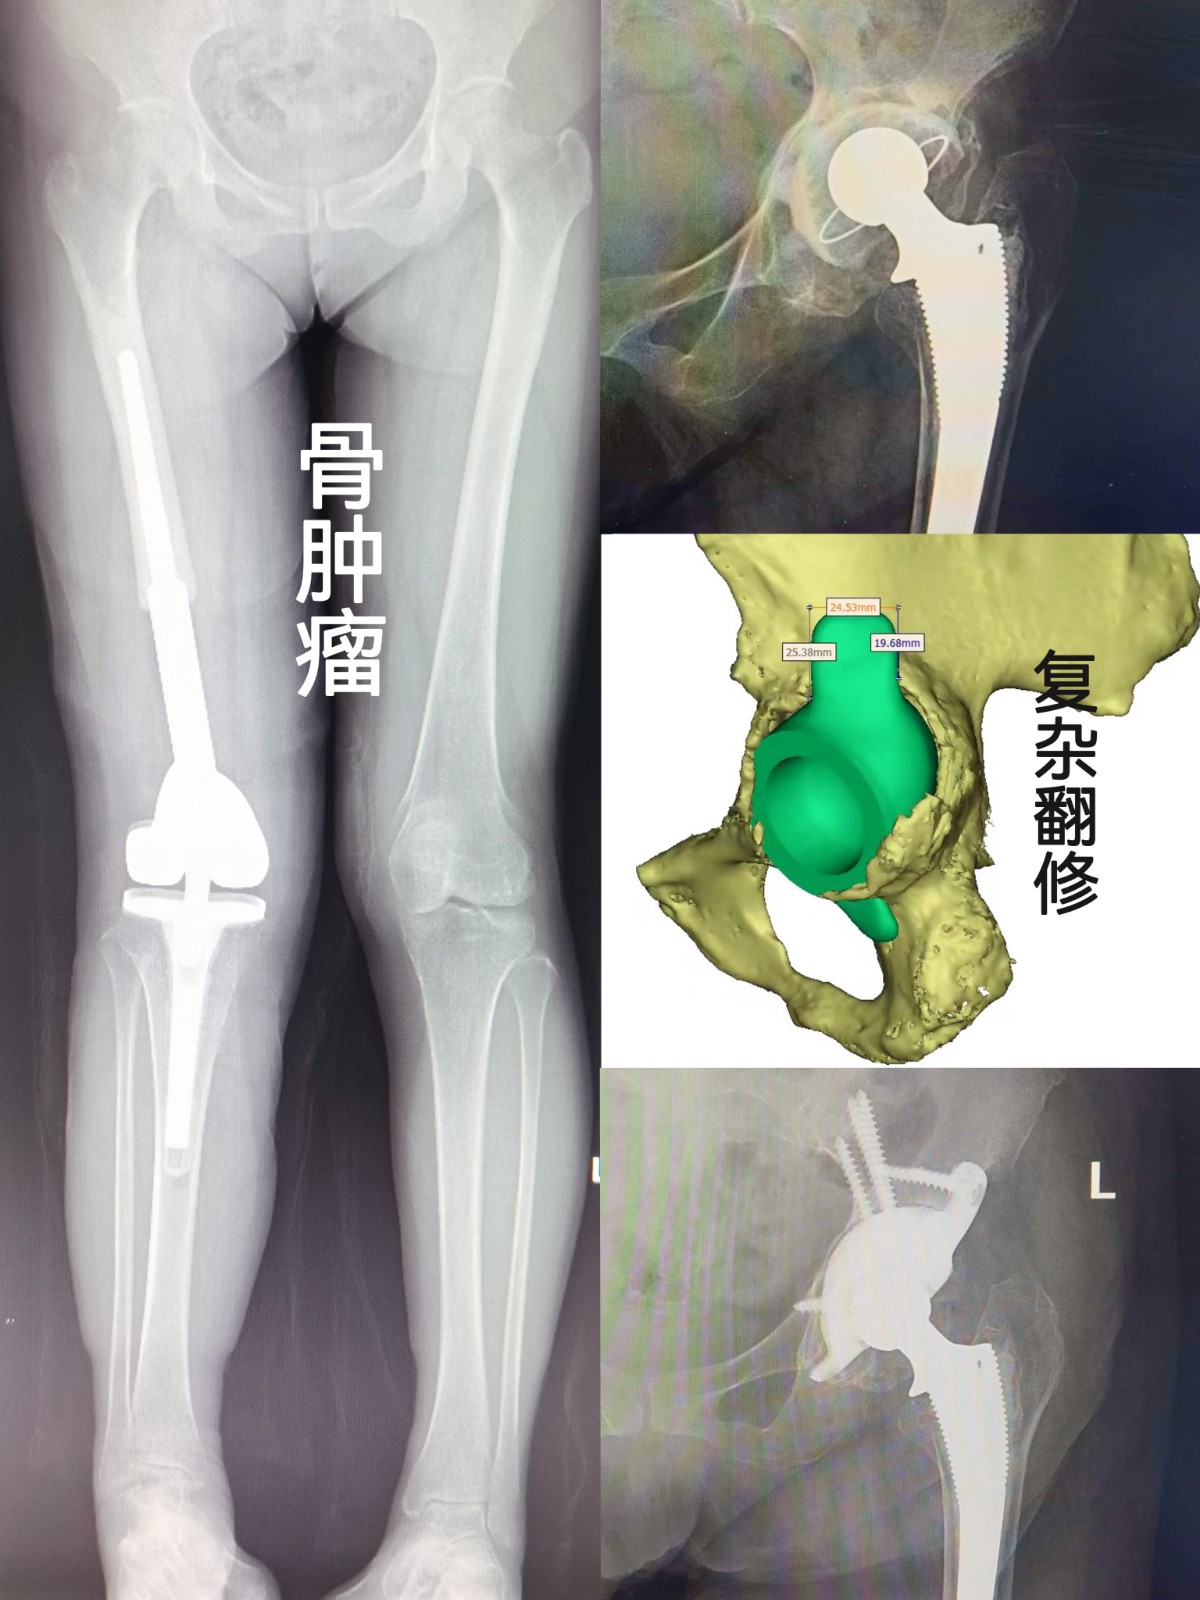

作為本地區(qū)創(chuàng)建最早的關節(jié)???,專業(yè)化特色明顯,關節(jié)手術復雜程度及手術量,均為本地區(qū)之最;可獨立開展各種肩、肘、腕、指、髖、膝、踝等關節(jié)的置換及翻修手術,特別擅長復雜髖、膝關節(jié)的置換、矯形、翻修,以及保膝階梯治療等。科室多年來在骨關節(jié)炎、關節(jié)畸形、股骨頭壞死,類風濕關節(jié)炎,強直性脊柱炎性關節(jié)病,髖關節(jié)發(fā)育不良,骨腫瘤,關節(jié)周圍骨折、脫位,以及關節(jié)運動損傷等疾患的治療中,積累了豐富的臨床經(jīng)驗。其中多種技術均為本地區(qū)首例獨家開展。

復雜髖翻修

首例關節(jié)置換